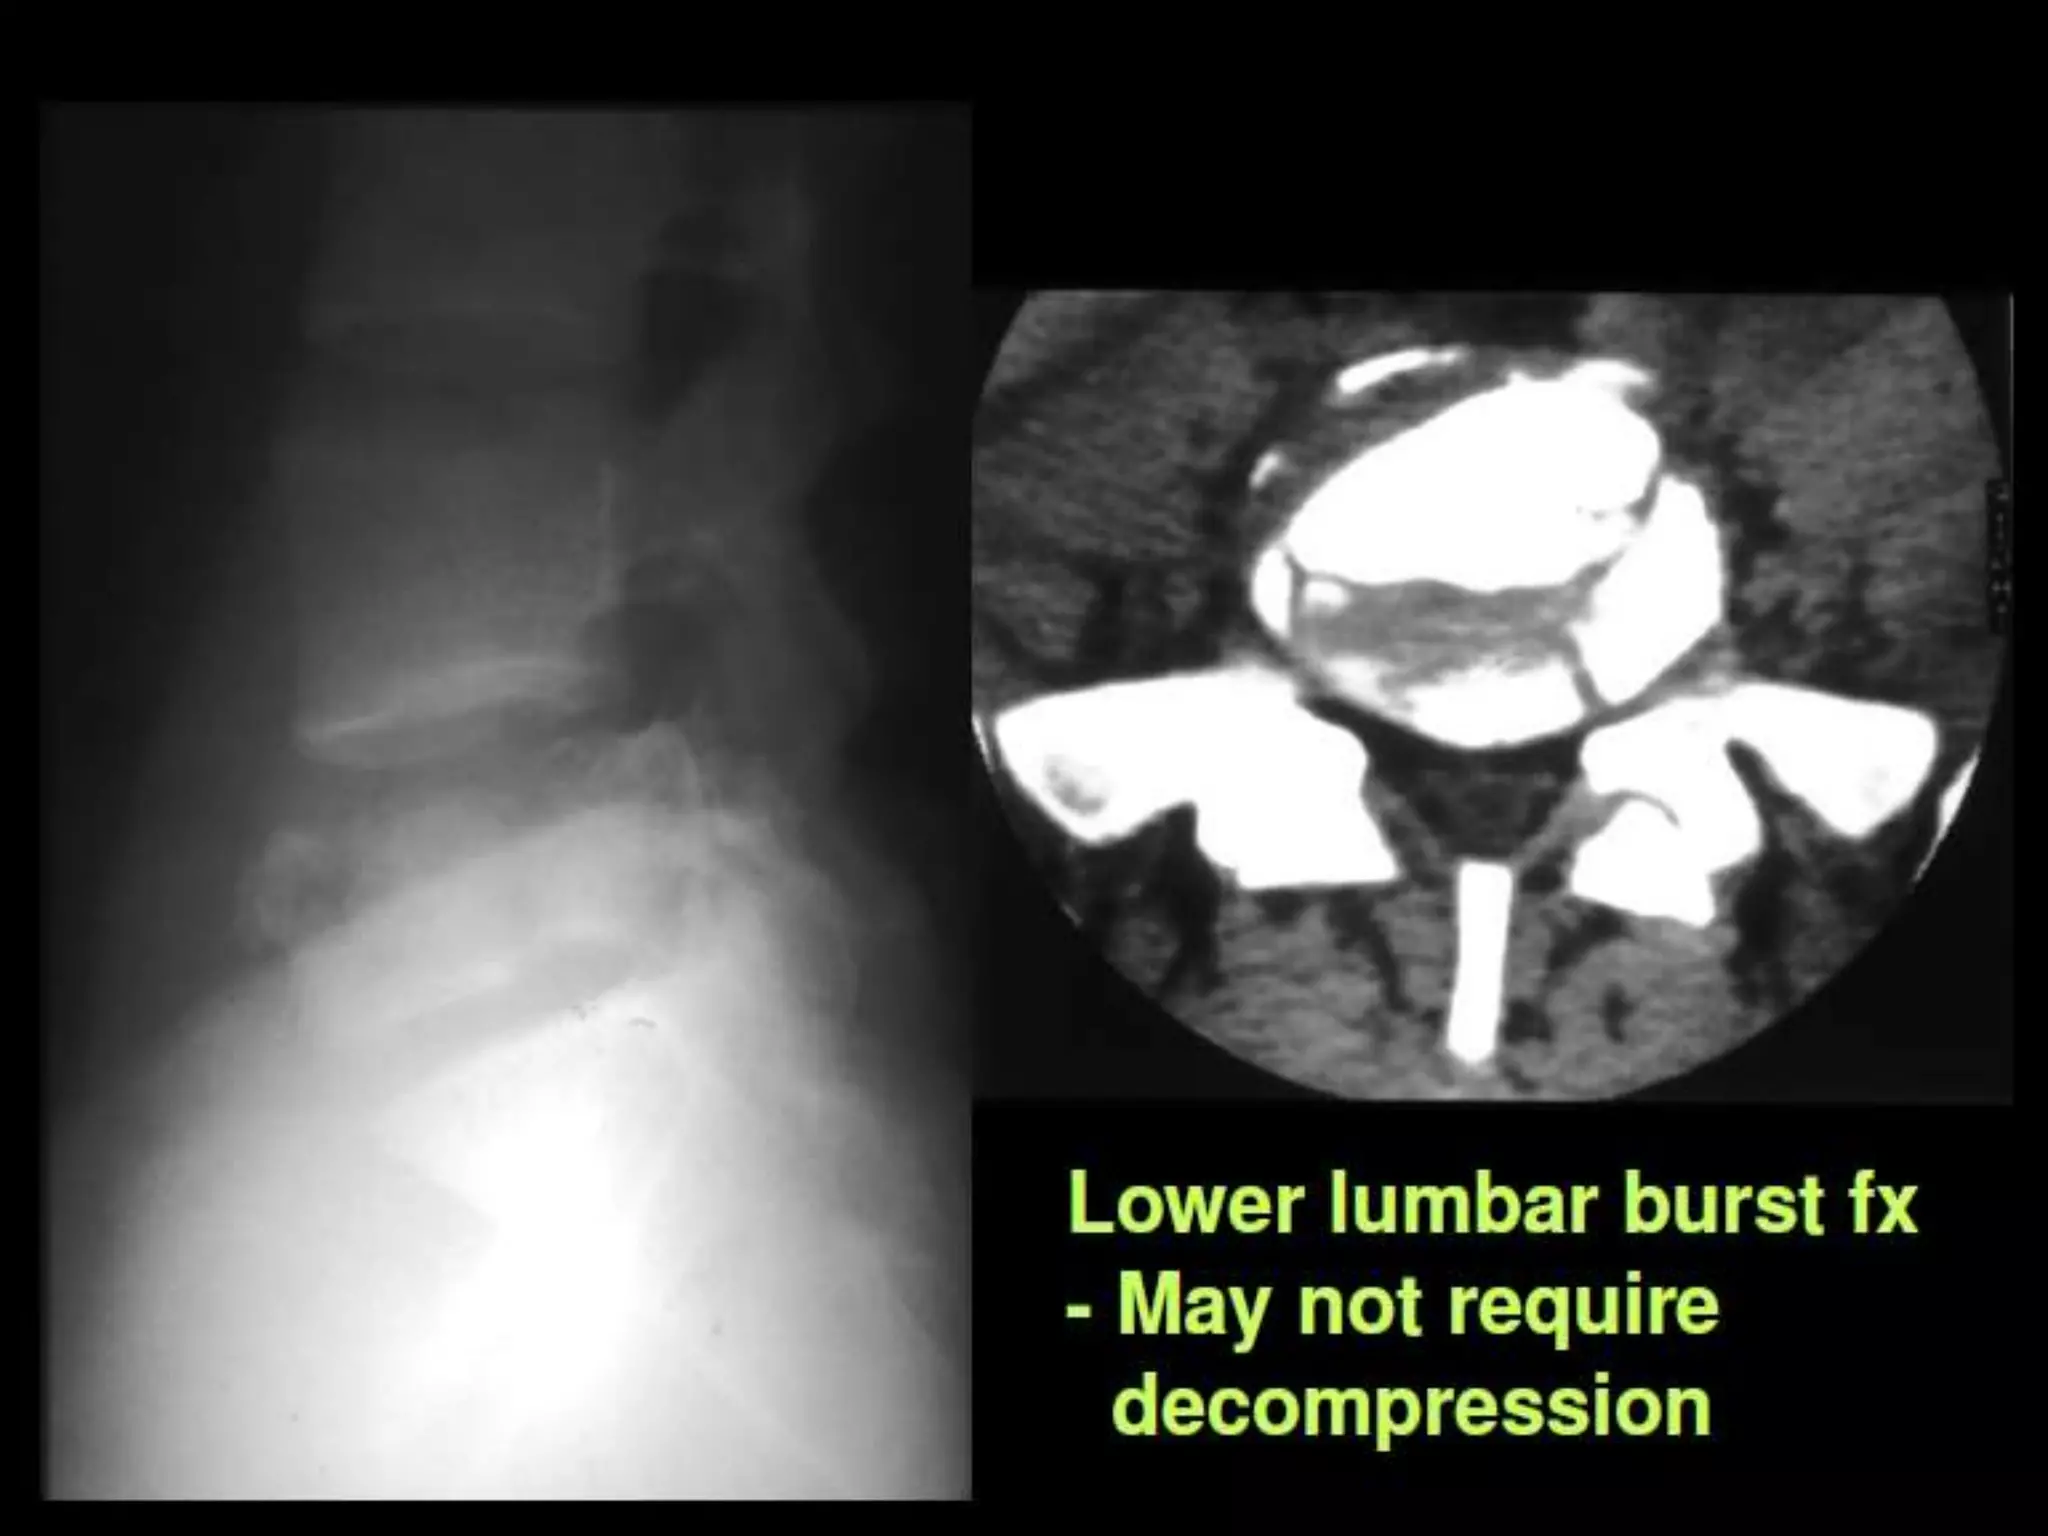

Coronal T2W image dorso lumbar spine of a 29 yr old male

patient showing burst fracture(arrow) of L3 vertebra.

Burst fracture.

Burst

fracture.

Burst vs. Anterior Wedge Fx:

• Anterior wedge - anterior column – stable.

• Burst - 2-3 columns – unstable.

• Important to differentiate.

– Look for posterior vertebral concavity.

– CT for evaluation of posterior vertebral body,

fracture of posterior elements.

– As many as 20% of burst fractures may be

missed if radiographs alone are used.

– MRI for ligamentous disruption / neuro sx.

Sagittal T2W

image of 23yr

old male

showing burst

fracture with

anterior

wedging(arrow)

of L1 vertebra.